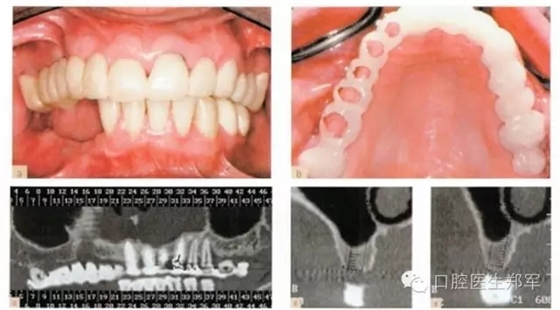

圖8 a暫時過渡性修復(fù)體 b復(fù)制暫時義齒制作放射導(dǎo)板(丙烯酸和硫酸鋇) c-e 放射導(dǎo)板下,阻射的牙齒的CT放射影像。 |

圖9上頜竇提升術(shù)中,放射導(dǎo)板作為外科導(dǎo)板以指導(dǎo)種植體的位置和方向。 |

圖10 a 下頜影像和外科導(dǎo)板。b-d 下頜CT中放射導(dǎo)板的位置 e 種植后的影像圖片 |